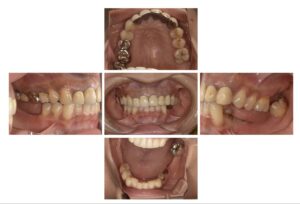

今回のインプラントは下顎臼歯部の欠損を主訴に来られた患者さんです。上顎にもむし歯があります。

今回もコンピュータガイドを使って1本1本埋入位置を確認していきます。インプラントを埋める本数やデザインは最も好ましい条件から最低限の条件まで提示し、患者さんと相談の上進めていきます。今回は3本のインプラントを埋入しました。

上顎前歯もやり変えてキレイに完成です。

本来ならば左上大臼歯を削って面を揃えたかったのですが、生活歯ということもありそのまま補綴しています。